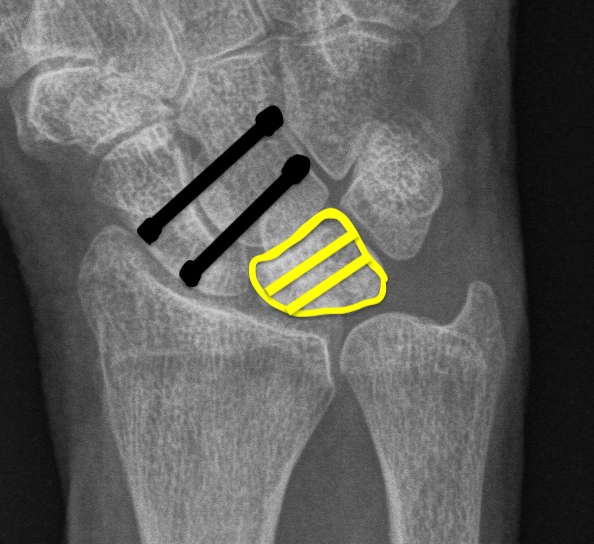

| Stage II | Stage IIIA |

|---|---|

| Sclerosis |

Collapse / fragmentation Normal carpal height |

![]() |

| Stage IIIB | Stage IV |

|

Collapse / fragmentation Scaphoid flexed / Capitate migrates proximally |

Pancarpal osteoarthritis |